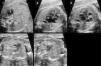

Así, la identificación de las cardiopatías congénitas es uno de los principales objetivos de la ecografía morfológica (18-22 semanas), pero una evaluación cardiaca fetal de 4 cámaras no ha obtenido tasas adecuadas de diagnóstico de cardiopatías congénitas12-14 y se propone ampliar esta exploración con una valoración cardiaca fetal básica ampliada, propuesta por Yagel (evaluación del abdomen fetal, de 4 cámaras, salida de grandes vasos y corte a nivel torácico de 3 vasos) (fig. 1), para mejorar los resultados15.

Exploración básica ampliada propuesta por Yagel. Nivel 1: corte abdominal. Nivel 2: corte de 4 cámaras. Nivel 3: corte de 5 vasos. Salida de aorta. Nivel 4: salida de arteria pulmonar con su bifurcación. Nivel 5: corte de 3 vasos+tráquea.

A: aorta; AD: aurícula derecha; AI: aurícula izquierda; APD: arteria pulmonar derecha; API: arteria pulmonar izquierda; E: estómago; H: hígado; P: arteria pulmonar; S: columna vertebral; SA: salida de aorta; T: tráquea; VCI: vena cava inferior; VCS: vena cava superior; VD: ventrículo derecho; VI: ventrículo izquierdo; VP: venas pulmonares.